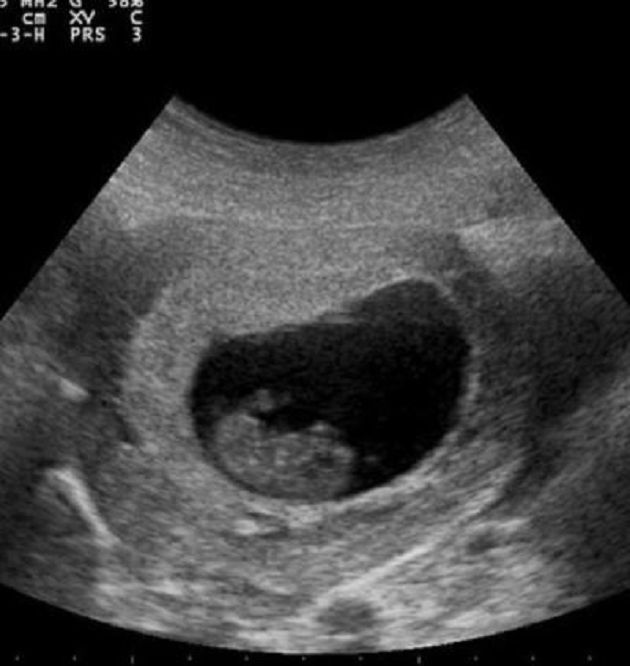

不料近日,IG帳號「boomsuyeon」突然發文,表示自己是秀妍,以模特兒身分活動時,就有額外的「工作」,以偶像身分出道後,「價碼」也跟著提高不少,選擇也變得更多,後來跟了一個中國的富豪金主,也住在中國一段時間,結果回到韓國後,居然發現自己懷孕了,但是金主卻不想負責。貼文中也特別附上超音波還有下半身的照片,短時間就引爆話題。

圖片來源/@bomsuyeon